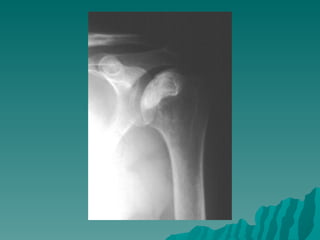

HASS’S HASTALIĞI

 HUMERUS  BAŞININ OSTEONEKROZU

 3 MAJOR BESLEYICI ARTER :

ARKUAT ARTER

POSTERİOR SİRKUMFLEKS DALI

ROTATOR KILIF DALLARI

HASS’S HASTALIĞI  HUMERUS BAŞININ OSTEONEKROZU  3 MAJOR BESLEYICI ARTER : ARKUAT ARTER POSTERİOR SİRKUMFLEKS DALI ROTATOR KILIF DALLARI